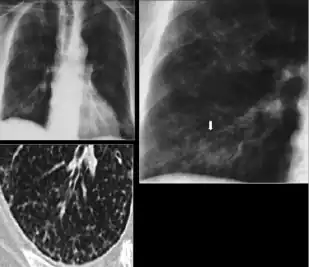

3. Nodule with poorly defined margins - Round density within the lung parenchyma, also called a tuberculoma. Nodules included in this category are those with margins that are indistinct or poorly defined (tree-in-bud sign[3]). The surrounding haziness can be either subtle or readily apparent and suggests coexisting airspace consolidation.

- Chest x-ray showing nodule with margins that are indistinct or poorly defined (tree-in-bud sign) in post-primary pulmonary TB.